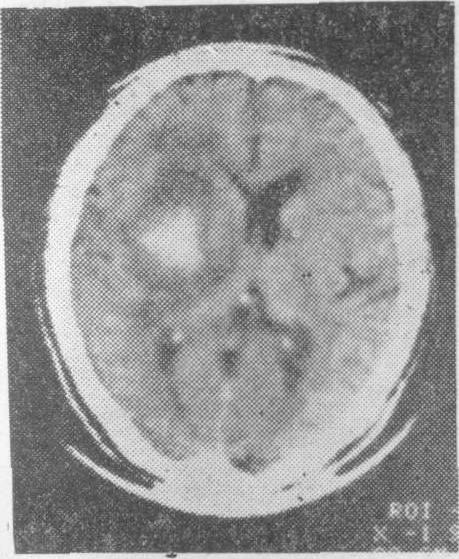

老年人脑血管病的诊断主要依靠详细询问病史,仔细观察临床症状和体征,并结合各种筛选检查。一般先用非创伤性检查,如脑电图、脑超声波、Doppler超声波、放射性核素脑扫描或计算机X线体层脑扫描检查等。特别是后者对老年人急性脑血管病的鉴别诊断更有帮助,可以鉴别是脑出血性病变(图3),脑缺血性病变(图4),抑或脑部肿瘤,以后根据需要再进行创伤性检查,如脑血管造影等。

老年人脑血管病的治疗首先应注意全身情况,因为老年人常并发心血管、肺部和肾脏疾病,在采用药物治疗,特别是肾功能不全时更应注意。出血性脑血管病的治疗包括降低颅内压,减轻脑水肿的药物如20%甘露醇、25%山梨醇或10%甘油静脉滴注,老年人用量和滴速视心、肾功能而定。止血药,特别是蛛网膜下腔出血可用6-氨基己酸静脉滴注。脑出血的外科手术在老年人应十分谨慎,仅对急性期过后,经内科治疗而出现视神经乳头水肿,颅内压仍继续增高,且血肿定位明确者,可考虑外科手术治疗。小脑出血病死率高,一旦确诊后唯一的治疗机X线体层脑扫描右侧基底节处有密度增高的出血灶,其周围有明显水肿,侧脑室向左移位方法是外科手术。缺血性脑血管病的治疗可用脑血管扩张剂以改善脑部血液循环,常用者有低分子右旋糖酐或羟乙基淀粉氯化钠溶液加入菸酸或罂粟碱等血管扩张剂静脉滴注,或血管扩张剂口服。抗凝治疗适合于短暂性脑缺血发作和进展性脑中风,可用肝素静脉滴注、新双香豆素、华法令或新抗凝片等口服。中国人口服抗凝片的剂量较国外文献所载的剂量为小,仅为1/3或1/2量。高龄患者应用时更要十分慎重。抗血小板粘聚药物可用潘生丁和阿斯匹林。缺血性脑血管病中,若颈内动脉颅外段出现血栓形成,可考虑动脉内膜血栓切除术或动脉内腔扩张术。颈内动脉颅内段及其分支狭窄或血栓形成,可考虑颈外-颈内动脉吻合术,即颞浅动脉、枕动脉或耳后动脉与大脑中动脉的皮层分支进行吻合术。椎-基底动脉狭窄或血栓形成时可考虑枕动脉和小脑后下动脉吻合手术。

图3 脑出血性病变的计算